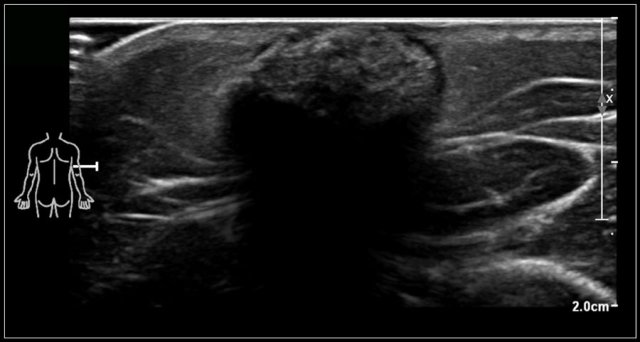

A six-month-old boy presented with a swelling in the left neck at birth.

Several ultrasound examinations could not differentiate between a hemangioma or a venous malformation.

At six months of age, the ultrasound showed a lesion, which was mostly composed of vessels which increased in size on straining.

On color Doppler the lesion showed increased flow while crying.

The final diagnosis on imaging and on clinical examination was a venous malformation.